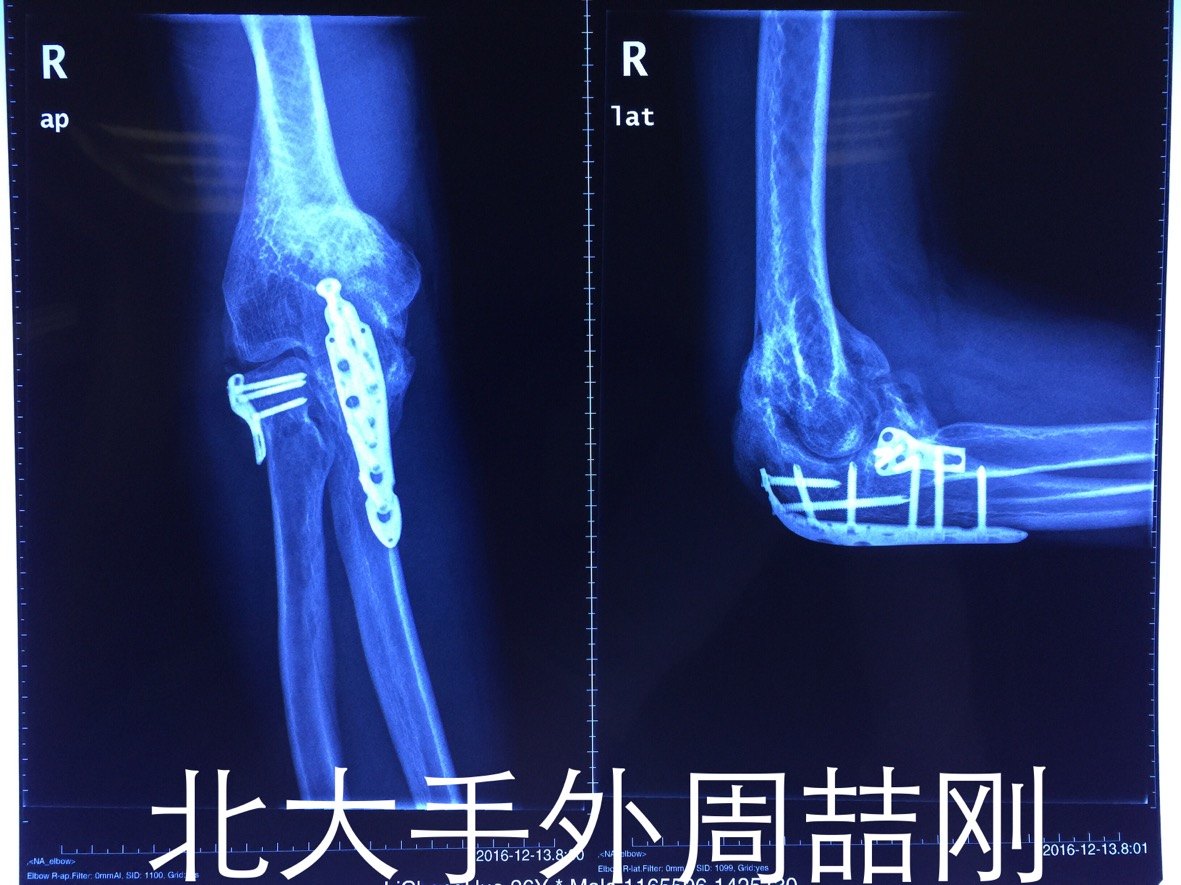

分享一例肘关节异位骨化的片子

患者一年前于外院行肘部骨折内固定术 术后出现异位骨化及肘关节僵硬